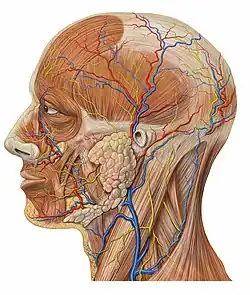

Sistema nervioso

El sistema nervioso está formado por el encéfalo, la médula espinal y los nervios periféricos. Los nervios pueden ser sensitivos que llevan información desde la periferia al encéfalo, motores que transportan señales desde el encéfalo a los músculos y mixtos que tienen fibras tanto sensitivas como motoras. La célula principal es la neurona que está dotada de prolongaciones que la unen a otras neuronas vecinas formando una compleja red de interconexiones. El sistema nervioso recoge información del mundo exterior a través de los sentidos o interna de los diferentes órganos, la procesa, y emite señales mediante los nervios motores que provocan la contracción de los músculos y el movimiento. También interviene en la producción de hormonas por las distintas glándulas (sistema neuroendocrino).[22][23]

Sistema circulatorio

El sistema circulatorio o sistema cardiovascular está formado por un fluido que se llama sangre, un conjunto de conductos (arterias, venas, capilares) y una bomba impulsora que es el corazón. Es un sistema de transporte interno que sirve para mover dentro del organismo elementos nutritivos, metabolitos, oxígeno, dióxido de carbono, hormonas y otras sustancias.[24] El sistema circulatorio humano, al igual que el de todos los mamíferos, es doble. La parte derecha del corazón envía la sangre no oxigenada hacia los pulmones a través de la arteria pulmonar, la sangre ya oxigenada es dirigida mediante las venas pulmonares hacia la parte izquierda del corazón que la distribuye por todo el cuerpo a través de la arteria aorta y sus ramas. La sangre se produce en la médula ósea roja, está formada por el plasma sanguíneo y los elementos formes que son plaquetas, glóbulos rojos(eritrocitos) y glóbulos blancos (leucocitos).